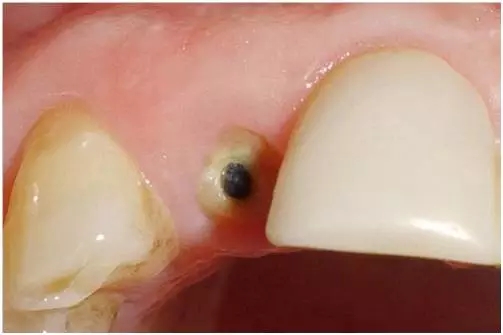

口內(nèi)檢查(圖1至4);

圖3:外傷9天后的臨床檢查:12牙牙冠在釉牙骨質(zhì)界水平處折斷。部分折斷面被牙齦覆蓋,可以看到中央有折斷的金屬根樁(鈦)。